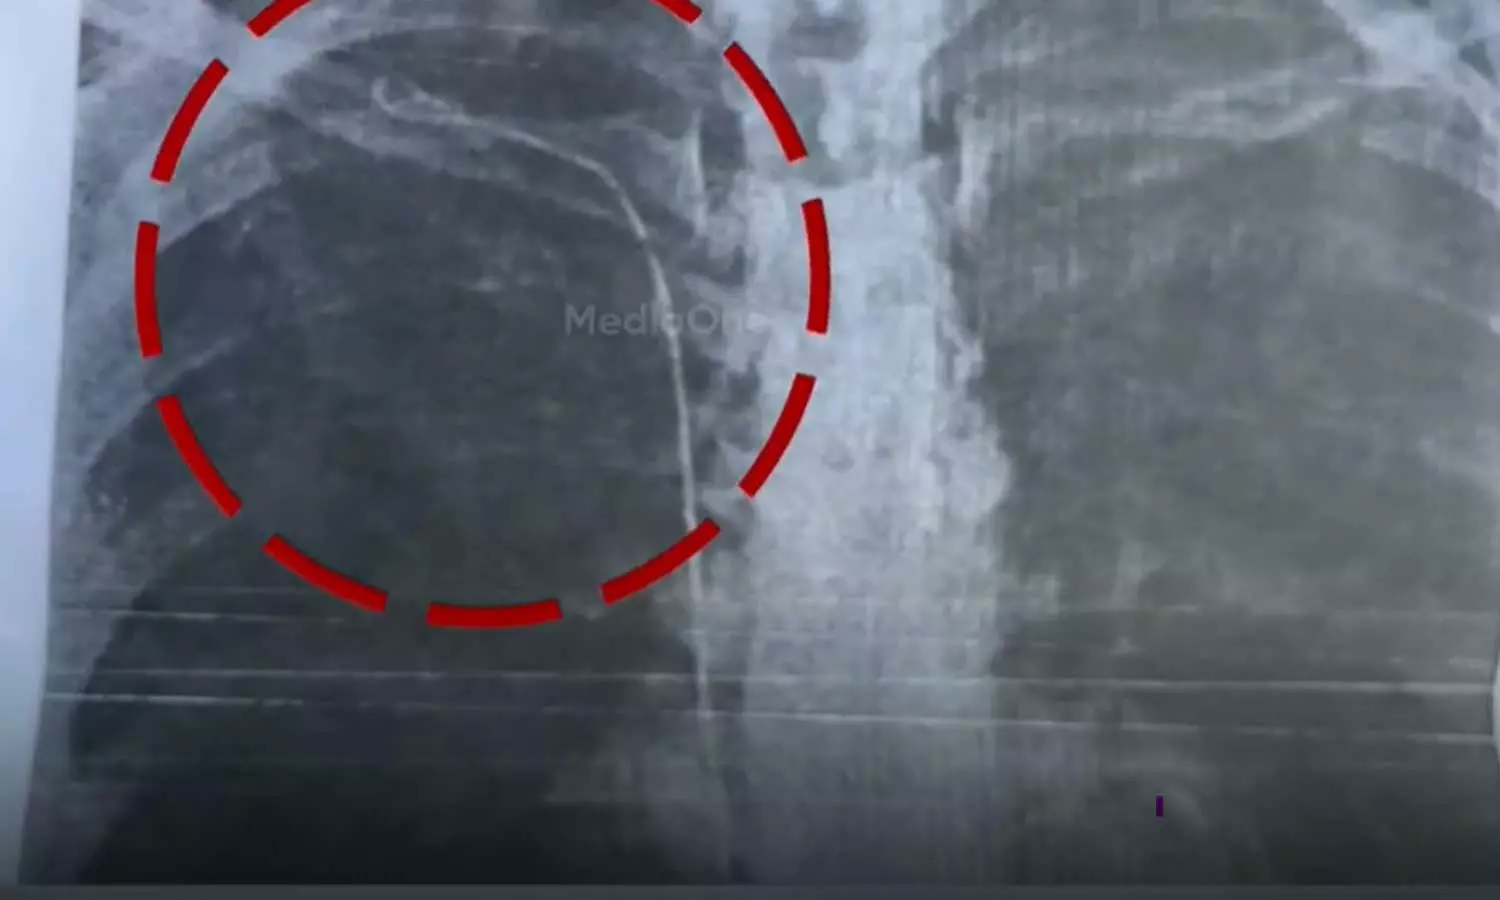

തൈറോയ്ഡ് ശസ്ത്രക്രിയക്ക് വിധേയയായ രോഗിയുടെ നെഞ്ചില് 50 സെന്റീമീറ്റര് നീളം വരുന്ന ട്യൂബാണുള്ളത്. ശ്വാസംമുട്ടലിനെ തുടര്ന്ന് നടത്തിയ പരിശോധനയിലാണ് ട്യൂബ് കണ്ടെത്തിയത്. 2023 മാര്ച്ചില് കാട്ടാക്കട മലയിന്കീഴ് സ്വദേശിനി സുമയ്യക്ക് നടത്തിയ ശസ്ത്രക്രിയയിലാണ് പിഴവെന്നാണ് ആരോപണം. ബന്ധുക്കള് ഡിഎംഒയ്ക്ക് പരാതി നല്കി.

നിലവില് ഡോക്ടര് കയ്യൊഴിഞ്ഞ സ്ഥിതിയെന്ന് സുമയ്യ ആരോപിച്ചു. ട്യൂബ് നീക്കം ചെയ്യാന് കഴിയാത്ത സാഹചര്യമെന്ന് മറ്റ് ഡോക്ടര്മാര് രോഗിയുടെ ബന്ധുക്കളെ അറിയിച്ചു. നടക്കാന് ബുദ്ധിമുട്ടും ശ്വാസംമുട്ടലും ഉണ്ടാകാറുണ്ടെന്നും എന്ന് രോഗി പറയുന്നു.